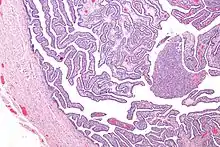

Definitive criteria include histopathologic evidence of endometritis, thickened filled Fallopian tubes, or laparoscopic findings. Gram stain/smear becomes definitive in the identification of rare, atypical and possibly more serious organisms.[22] Two thirds of patients with laparoscopic evidence of previous PID were not aware they had PID, but even asymptomatic PID can cause serious harm.